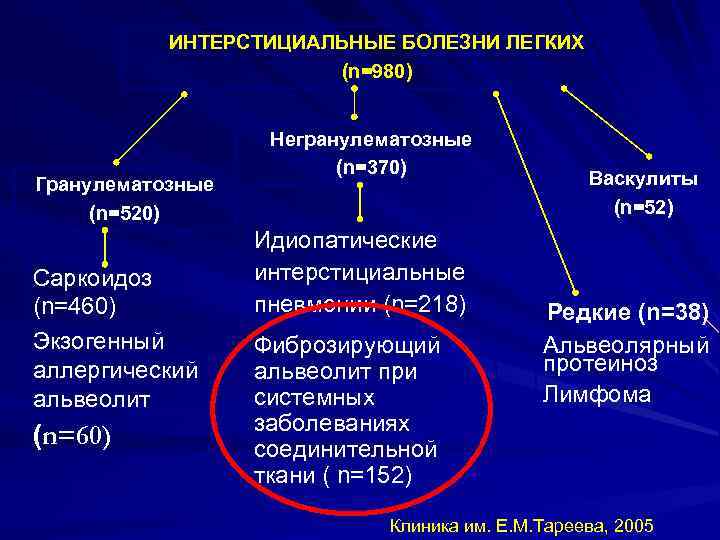

Дифференциальная диагностика заболеваний плевры